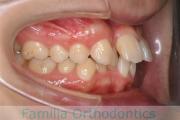

上顎

下顎

前歯の関係など

右側

正面

左側